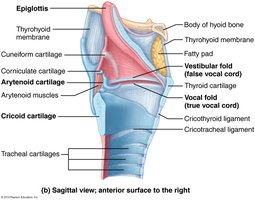

Larynx

The larynx connects the pharynx to the trachea and is responsible for sound production. It is composed of several cartilages, including the epiglottis (covers airway during swallowing), thyroid cartilage (Adam's apple), and cricoid cartilage (only complete ring).

Glottis: Opening between the true vocal cords, which vibrate to produce sound.

False Vocal Cords: Vestibular folds, found laterally to the glottis.